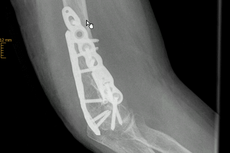

Ellenhakenbruch (Olekranonfraktur)

Das Olekranon ist das ellenbogenseitige Ende der Elle (Ulna). Hier befestigt sich die Sehne des Unterarmstreckers (Trizepsmuskel) und überträgt so die Kraft der Streckmuskulatur auf das Olekranon und den Unterarm.

Frakturen des Olekranons sind häufig, sie können einfach aber auch sehr komplex sein.

Ein stabiler Ellenbogenbruch (Olekranonfraktur), bei dem die Bruchstücke nur minimal voneinander entfernt liegen und keine Verschiebung aufweisen, kann nicht operativ (konservativ) behandelt werden. In diesem Fall wird der betroffene Arm im Gips oder in einer Orthese ruhig gestellt.

Ist dieses nicht der Fall und es liegt eine komplexe Fraktur mit verschobenen Knochenfragmenten vor, erfolgt in der Regel eine Operation. Durch den Zug der Streckmuskulatur klaffen die einzelnen Bruchstücke weit auseinander. Zur Fixierung der Fraktur und Wiederherstellung der Gelenkfunktion ist eine Verdrahtung oder Verplattung des Bruchs notwendig.